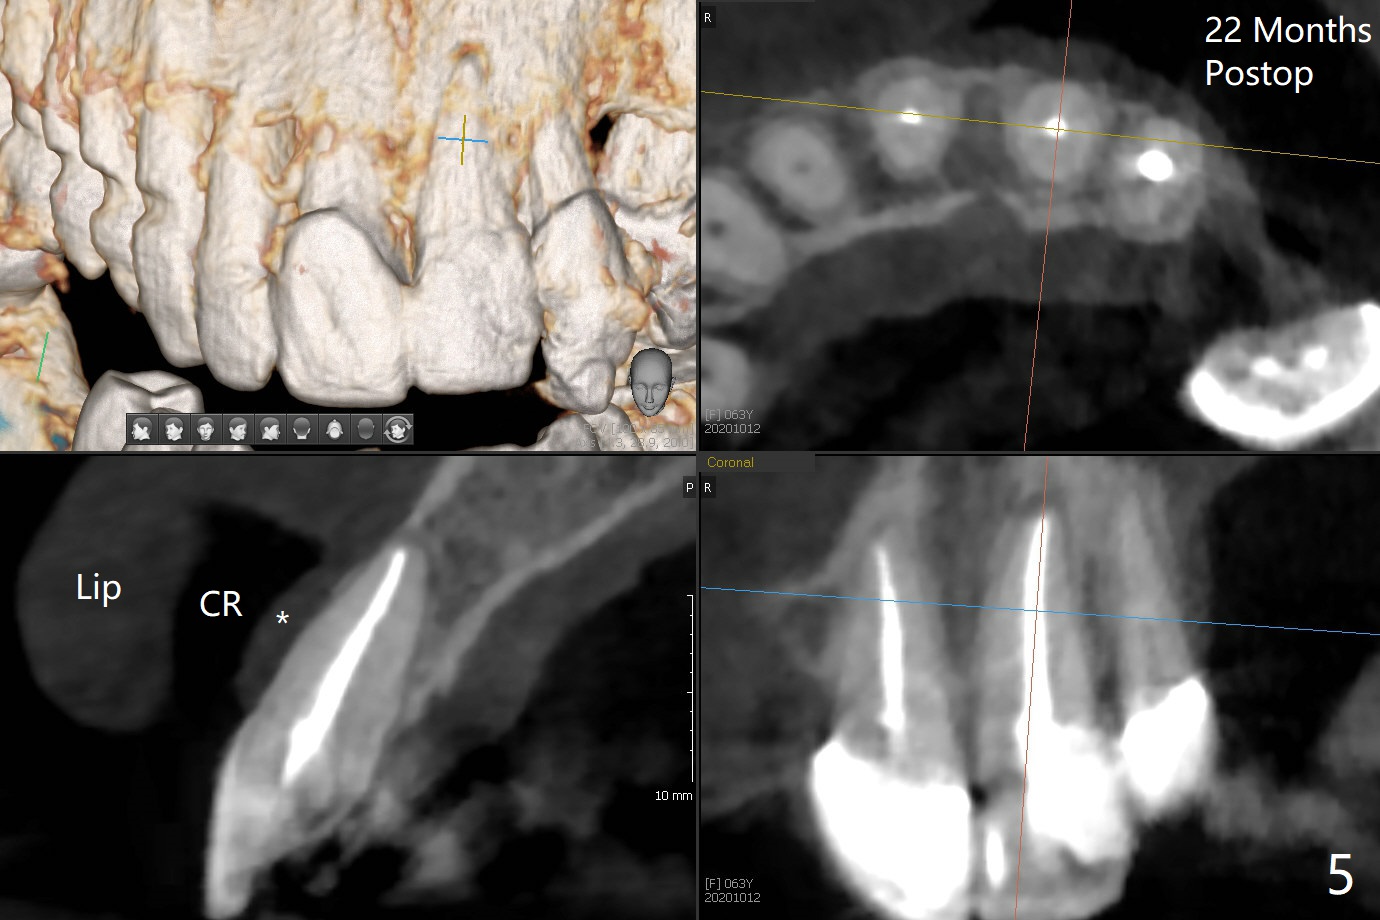

62岁女因牙痛(图一)做根管治疗(图二,三)。一年10个月后因11,13,30,31 植牙,拍摄CT,根尖阴影明显缩小(图四,五)。颊侧骨板薄而短(图四:>),牙槽骨也狭窄,如果需要植牙,比较困难。